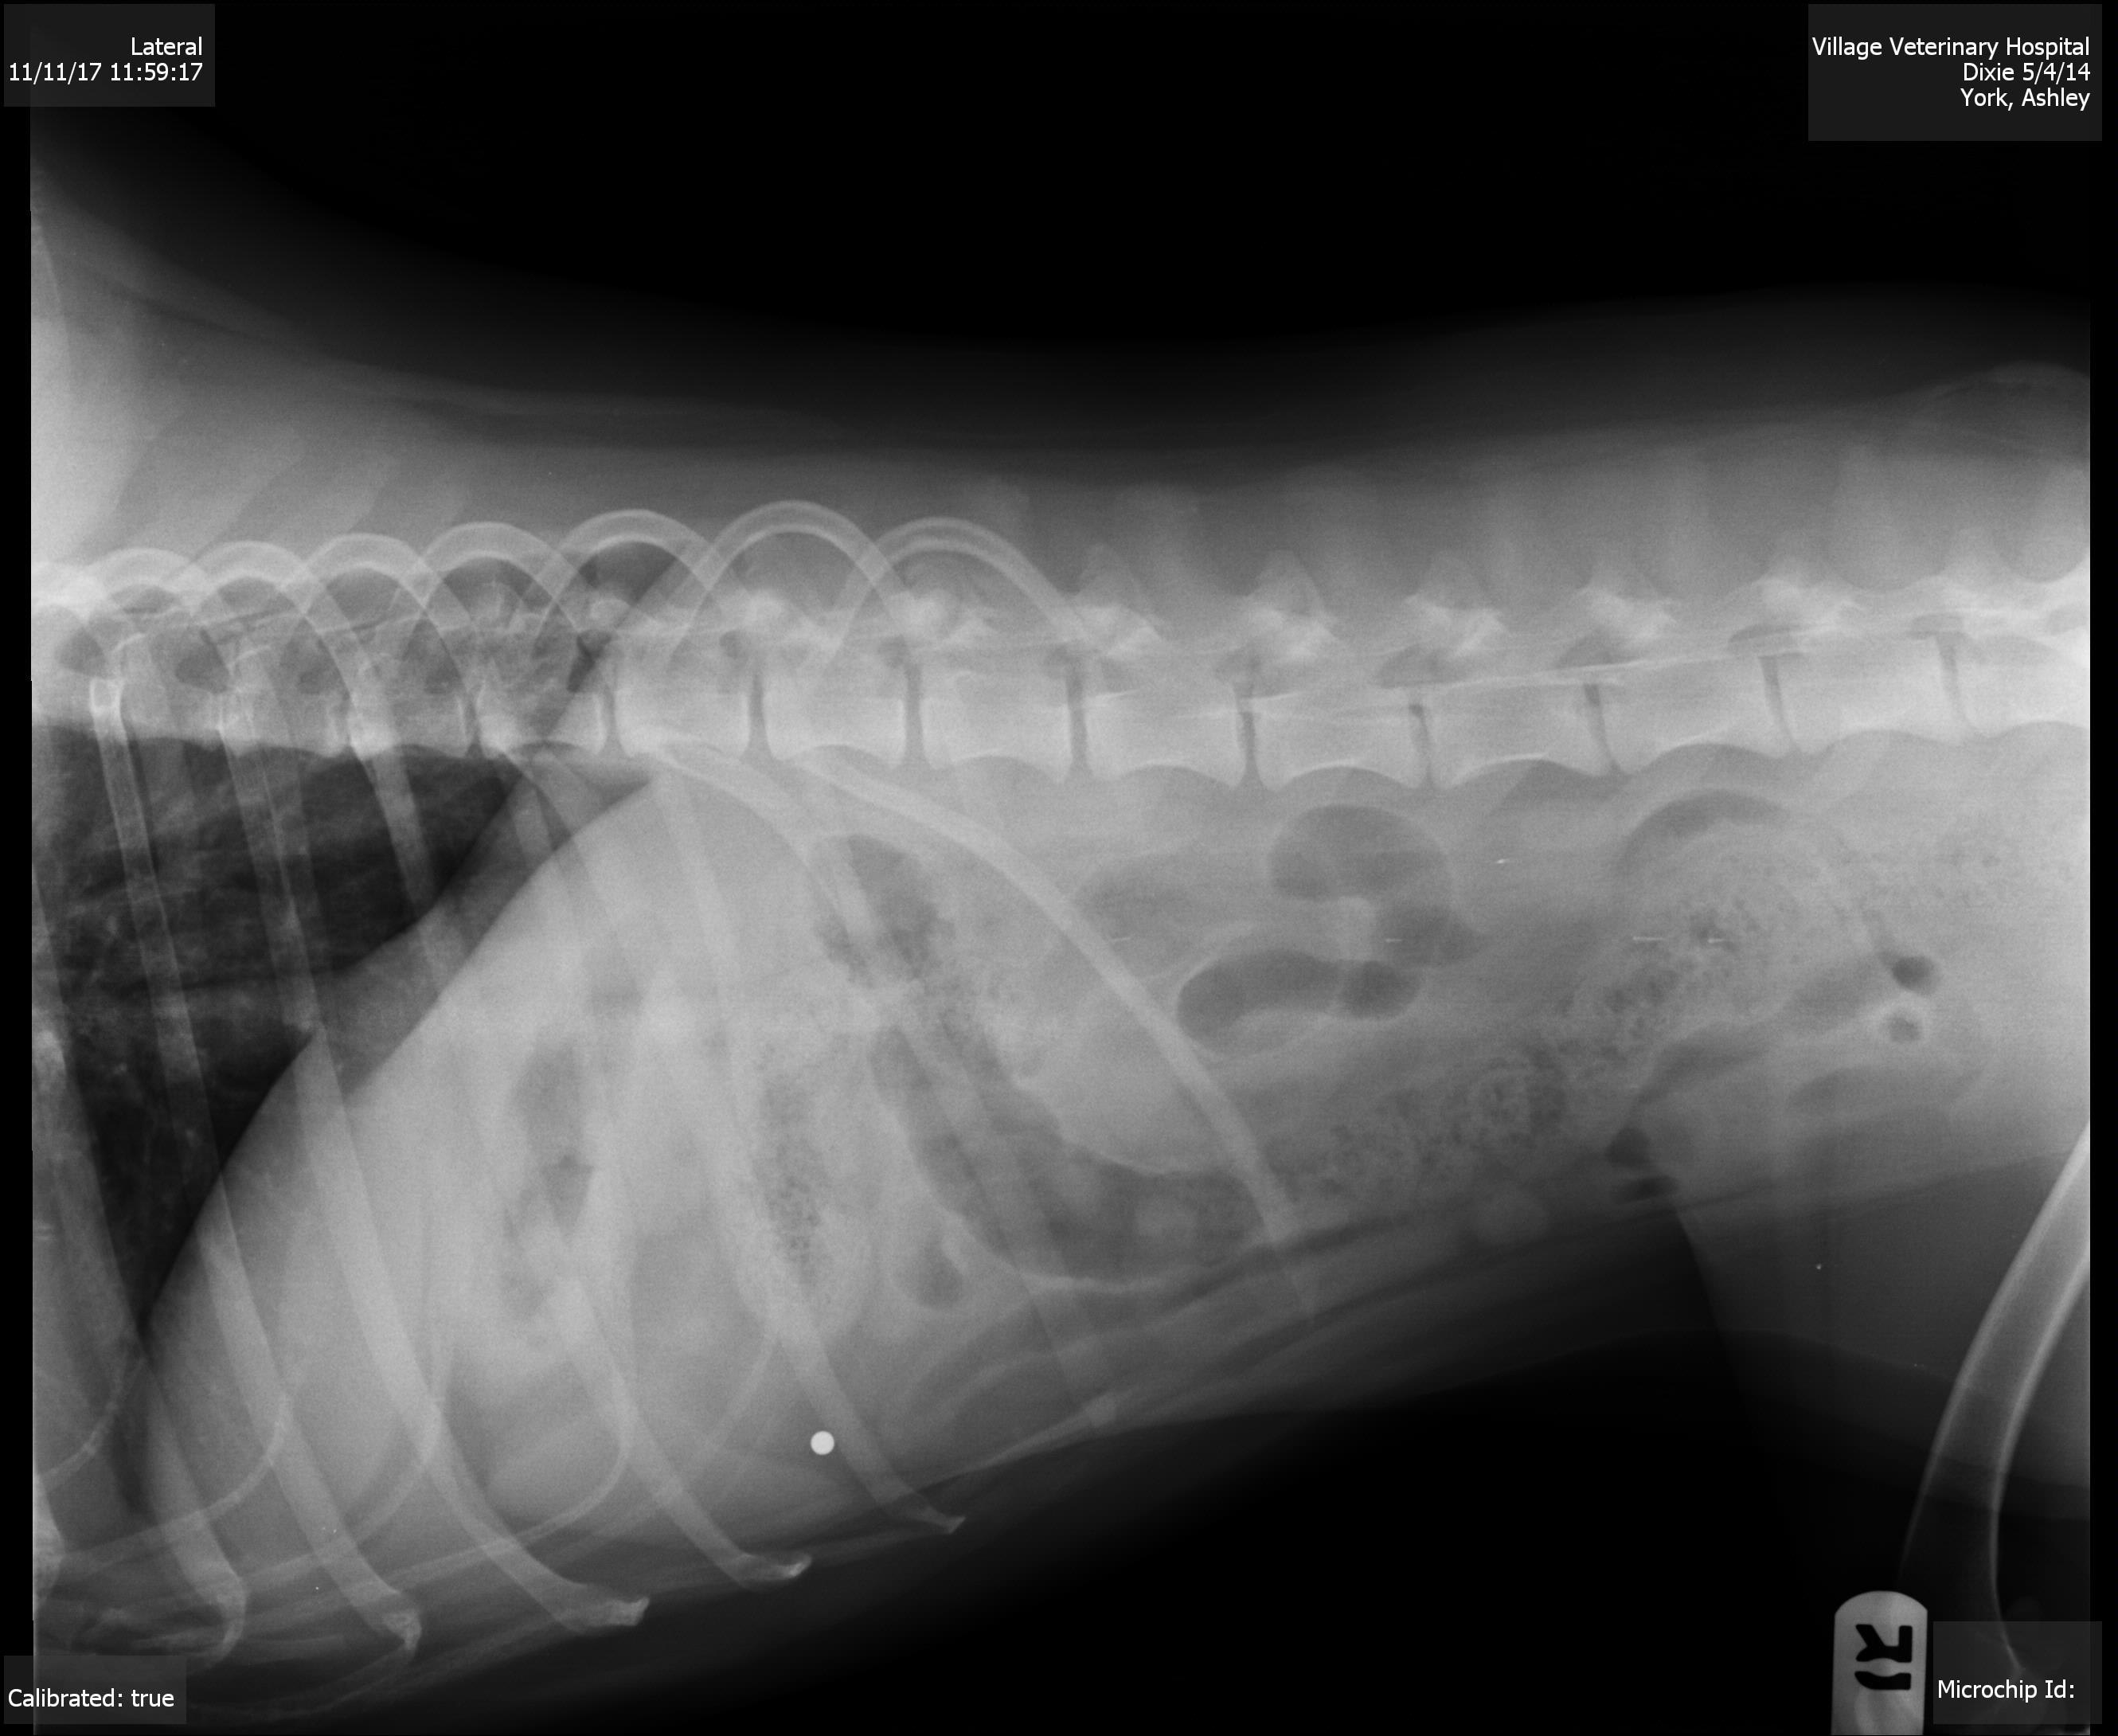

My dog keeps gagging/choking & licking/swallowing a lot,this started last Wed,she threw up bile Wed.morning,ate dinner that night,threw up bile Thurs.morning & night & did not eat all day Thurs,ate Fri,hasn't vomited since but still not much of an appetite & keeps gagging,we ran a chem17 w/lytes & that came back normal besides she was 0.1 low from norm. on her potassium levels,we took an xray of her abdomen & that looks fine as well, other than waiting until Mon to do chest xrays idk what todo

I am sorry that Dixie is so sick. In this type of situation I am still usually very suspicious of an intestinal foreign object. There is one area on the x-Ray that is a little suspicious to me. Make sure to look under her tongue for any thread or string caught. I would typically recommend either a barium series or an abdominal ultrasound at this time. Occasionally exploratory surgery is recommended if we can’t find another answer . Best of luck and I hope she improves soon.